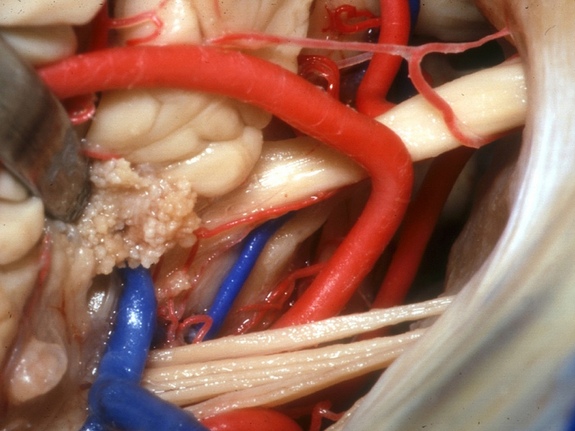

Mira hacia abajo en el quiasma óptico, un sitio que juega un papel importante en la vista. El quiasma óptico es la parte del cerebro donde se entrecruzan parcialmente las fibras axónicas de los nervios ópticos.

Este grupo de nervios y arterias se reúnen en el “ángulo pontocerebeloso,” un punto de unión entre el cerebelo y la protuberancia. Parte del tronco cerebral, la protuberancia se encarga de mediar todas las transferencias de mensajes entre el cerebelo y el resto del cerebro.